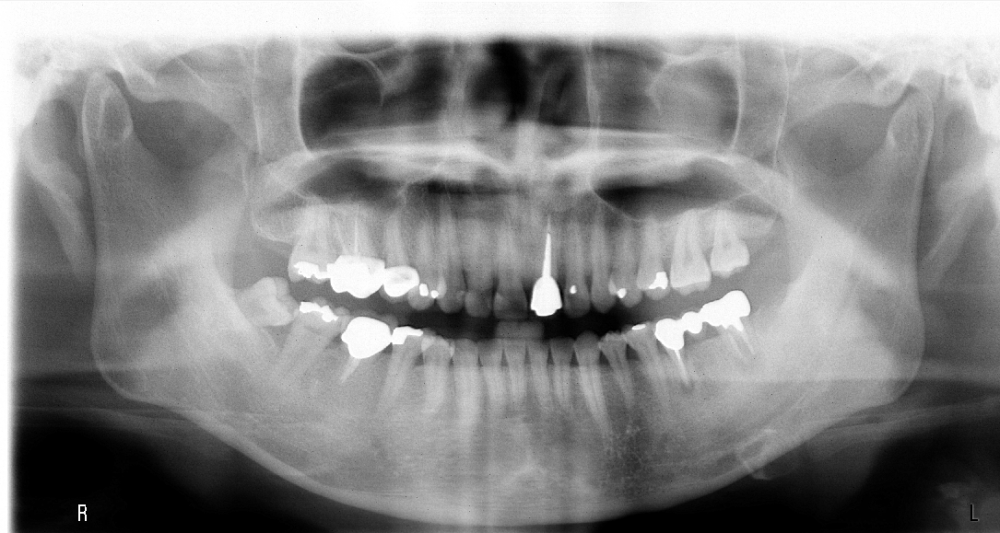

患者陳先生於91/06/03初診,為一個牙周病患者,合併有右下缺牙。經過保守性牙周處理後,於91/08/14放置右下三顆植體。

完成後大約半年至一年進行一次例行性追蹤檢查,並無特別問題。以下為96/08/13時的追蹤小片,可以見到當時三顆植體的骨高度並無顯著變化。但右下第一小臼齒此時發現有搖動度增加的情形,當時對該顆牙做了咬合調整,降低咬合功能負荷,希望能有所改善。

患者之後於96/11/08在右下第一小臼齒與植體間有膿胞產生,並於97/02/21確認右下第一小臼齒有根裂的情形,因此在97/02/29拔除此牙;經過將近半年後,於97/09/23放置一顆植體於此位置

97/02/21 確定根裂時拍的片子

97/09/18 拔牙半年後安排右下第一小臼齒植牙前

97/09/23 右下第一小臼齒植牙完成時

直到經過一年半後,於99/07/19又有明顯發炎,拍攝追蹤片,發覺連同更遠心的那顆植體的骨頭也破壞下降了

99/07/19

和患者積極溝通,由於患者神經管上的骨高度並不理想,建議積極移除中間兩顆有問題的植體重放,阻止發炎與骨破壞繼續下降;但患者想再追蹤。

患者於99/10期間因起床後有暈倒現象,住院後持續吃抗凝血劑,雖有發炎但不致於不舒服,因此一直不願積極處理;終於在100/03/1將兩顆植體移除,並於100/05/23回診評估再次植牙的條件。

100/05/23

於100/06/07重新放置兩顆植體

並於100/10/25將中間兩顆植體做二階接出

100/11/21 補綴完成